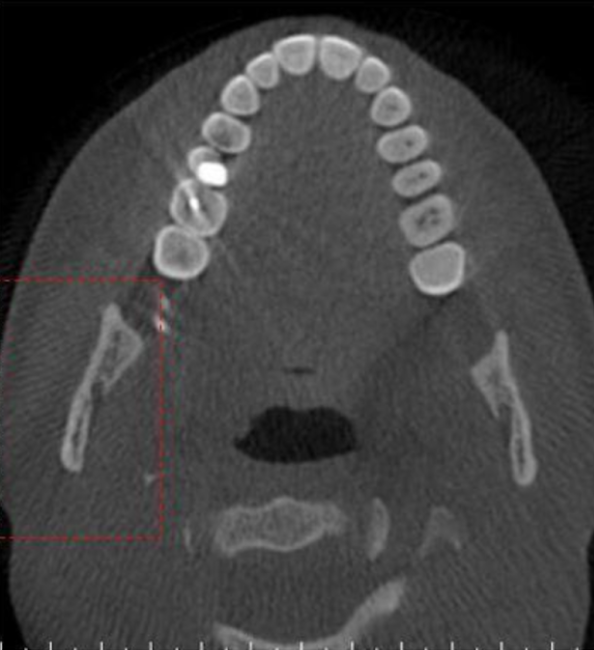

axial

what plane is this

level of maxilla (above maxillary teeth)

at what level is this

maxilla

which arch is this